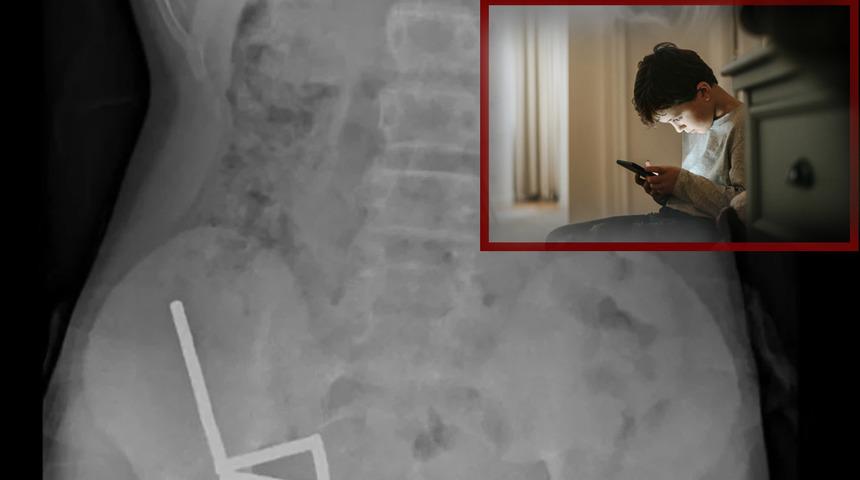

Çekilen röntgen görüntüleri, mıknatısların bağırsaklarda dört ayrı düz çizgi halinde kümelendiğini ve manyetik kuvvetler nedeniyle farklı bağırsak bölümlerinin birbirine yapıştığını ortaya koydu.

Doktorlar, mıknatısların bağırsaklarda ciddi hasara yol açtığını tespit etti. Çocuğun bağırsağının bir bölümü ve mıknatıslar cerrahi müdahaleyle çıkarıldı. Operasyon, tıp literatürüne geçti.